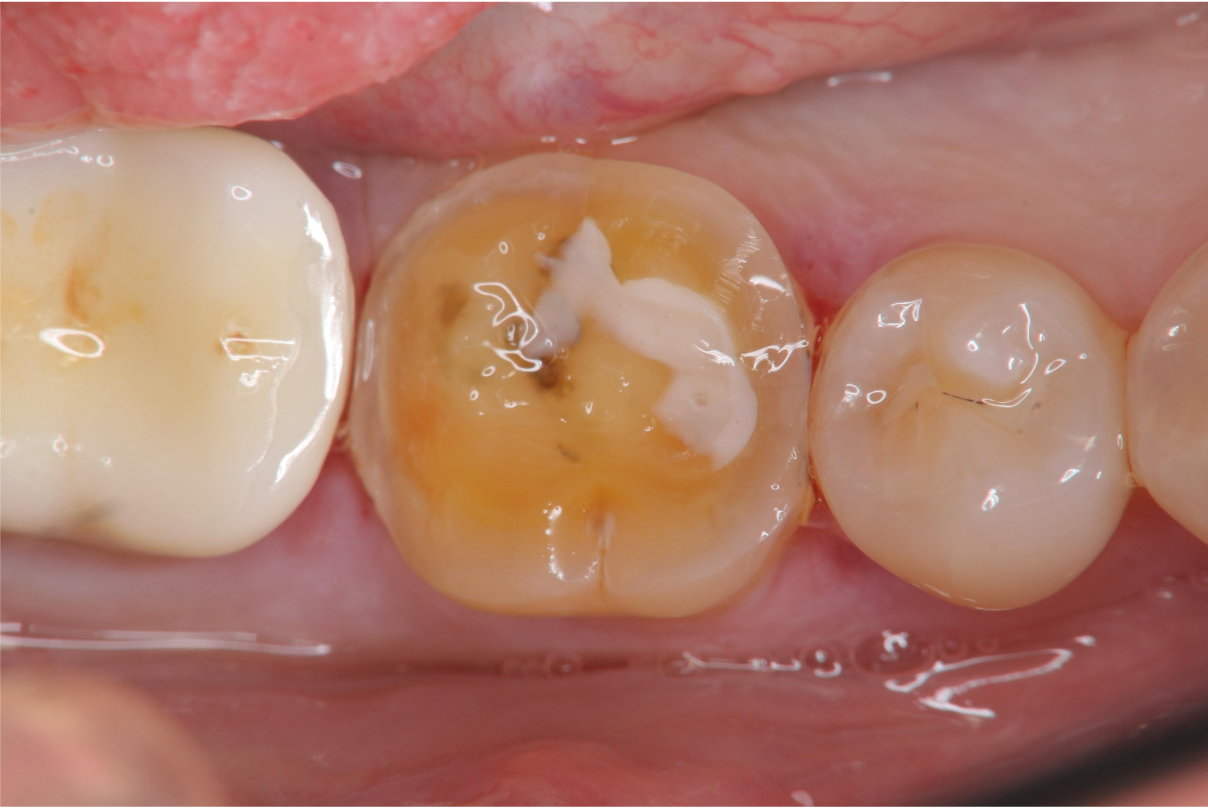

牙髓未受侵犯

冠塊體牙齒製備